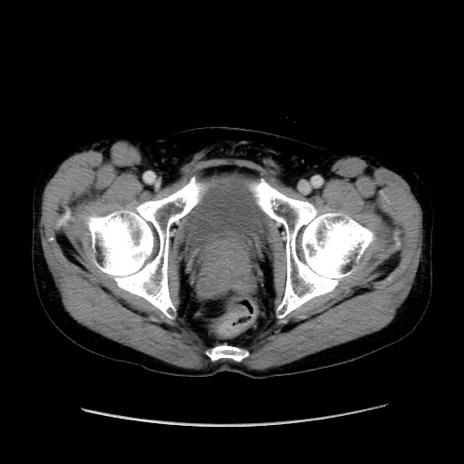

症例37(横断像)

【症例】40歳代 男性

【主訴】腹痛

【現病歴】4時間ほど前に電車に乗車中に臍部上より腹痛出現。徐々に増悪し起立困難となり、救急外来受診。生ものは数日食べていない。今朝お雑煮を食べた。

【身体所見】BT 36.8℃、BP 117/84mmHg、HR 91/min、SpO2 97%、苦悶様、腹部:臍上部広範囲圧痛あり、反跳痛±

【データ】WBC 8100、CRP 0.03